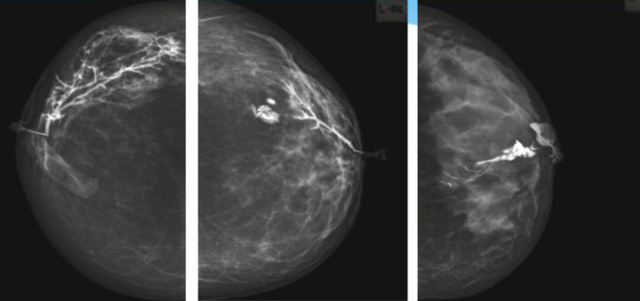

乳腺導(dǎo)管內(nèi)乳頭狀瘤分為以下兩個,位于乳暈區(qū)大導(dǎo)管的中央型乳頭狀瘤,起源于末梢導(dǎo)管小葉單位的外周型乳頭狀瘤。外周型乳頭狀瘤常常沒有明顯的的臨床表現(xiàn),常因X線或乳腺超聲設(shè)備檢查發(fā)現(xiàn)。重點(diǎn)要關(guān)注的是中央型乳頭狀瘤,發(fā)生于任何年齡的女性,以40~50歲者居多。它表現(xiàn)為:單側(cè)乳頭溢液,特別是血性溢液少數(shù)病人可在乳暈區(qū)觸及腫塊。從病理學(xué)上面講表現(xiàn)為導(dǎo)管上皮和間質(zhì)增生形成有纖維脈管束的乳頭狀結(jié)構(gòu)。這是它一個病理學(xué)上的表現(xiàn)。它的超聲表現(xiàn)為:病變導(dǎo)管囊狀擴(kuò)張呈無回聲,內(nèi)可見乳頭狀低回聲或中等回聲。乳暈處的導(dǎo)管擴(kuò)張,管腔內(nèi)可見邊界清楚的,低回聲實(shí)性結(jié)節(jié)。外周型導(dǎo)管內(nèi)乳頭狀瘤可,表現(xiàn)擴(kuò)張為為低回聲的實(shí)性結(jié)節(jié),CDFI:部分腫瘤可顯示為軸心性的看到血流信號。乳腺增生癥:可見導(dǎo)管擴(kuò)張,內(nèi)無乳頭狀實(shí)性回聲,導(dǎo)管內(nèi)乳頭狀癌:囊內(nèi)乳頭狀癌病變較大,不規(guī)則,厚基底,血流豐富。以囊性為主的混合回聲,形態(tài)不規(guī)則,內(nèi)見實(shí)性低回聲實(shí)性低回聲可見少量血流,病理為囊內(nèi)乳頭狀癌。

乳腺超聲設(shè)備檢查的價值在哪里呢?它可以檢查發(fā)現(xiàn)乳暈周圍的各種病變,對于單側(cè)乳頭溢液、血性溢液的患者,超聲是首選的影像學(xué)檢查方法。注意:導(dǎo)管內(nèi)乳頭狀瘤可合并不典型增生或,導(dǎo)管內(nèi)乳頭狀癌,手術(shù)前懷疑時候,就應(yīng)該手術(shù)切除而不是用微創(chuàng)手術(shù)。